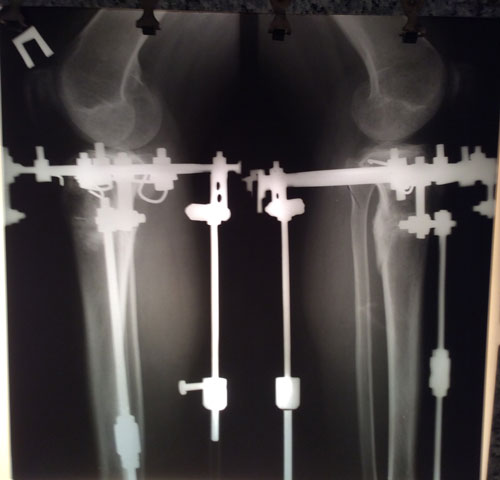

Рентген в 90 дней.

IMG_2518-10-05-17-11-17.JPG

IMG_2519-10-05-17-11-17.JPG

Дата операции 10.02.2017г.

Дата снятия аппаратов 10.05.2017г.

Срок лечения 90 дней.